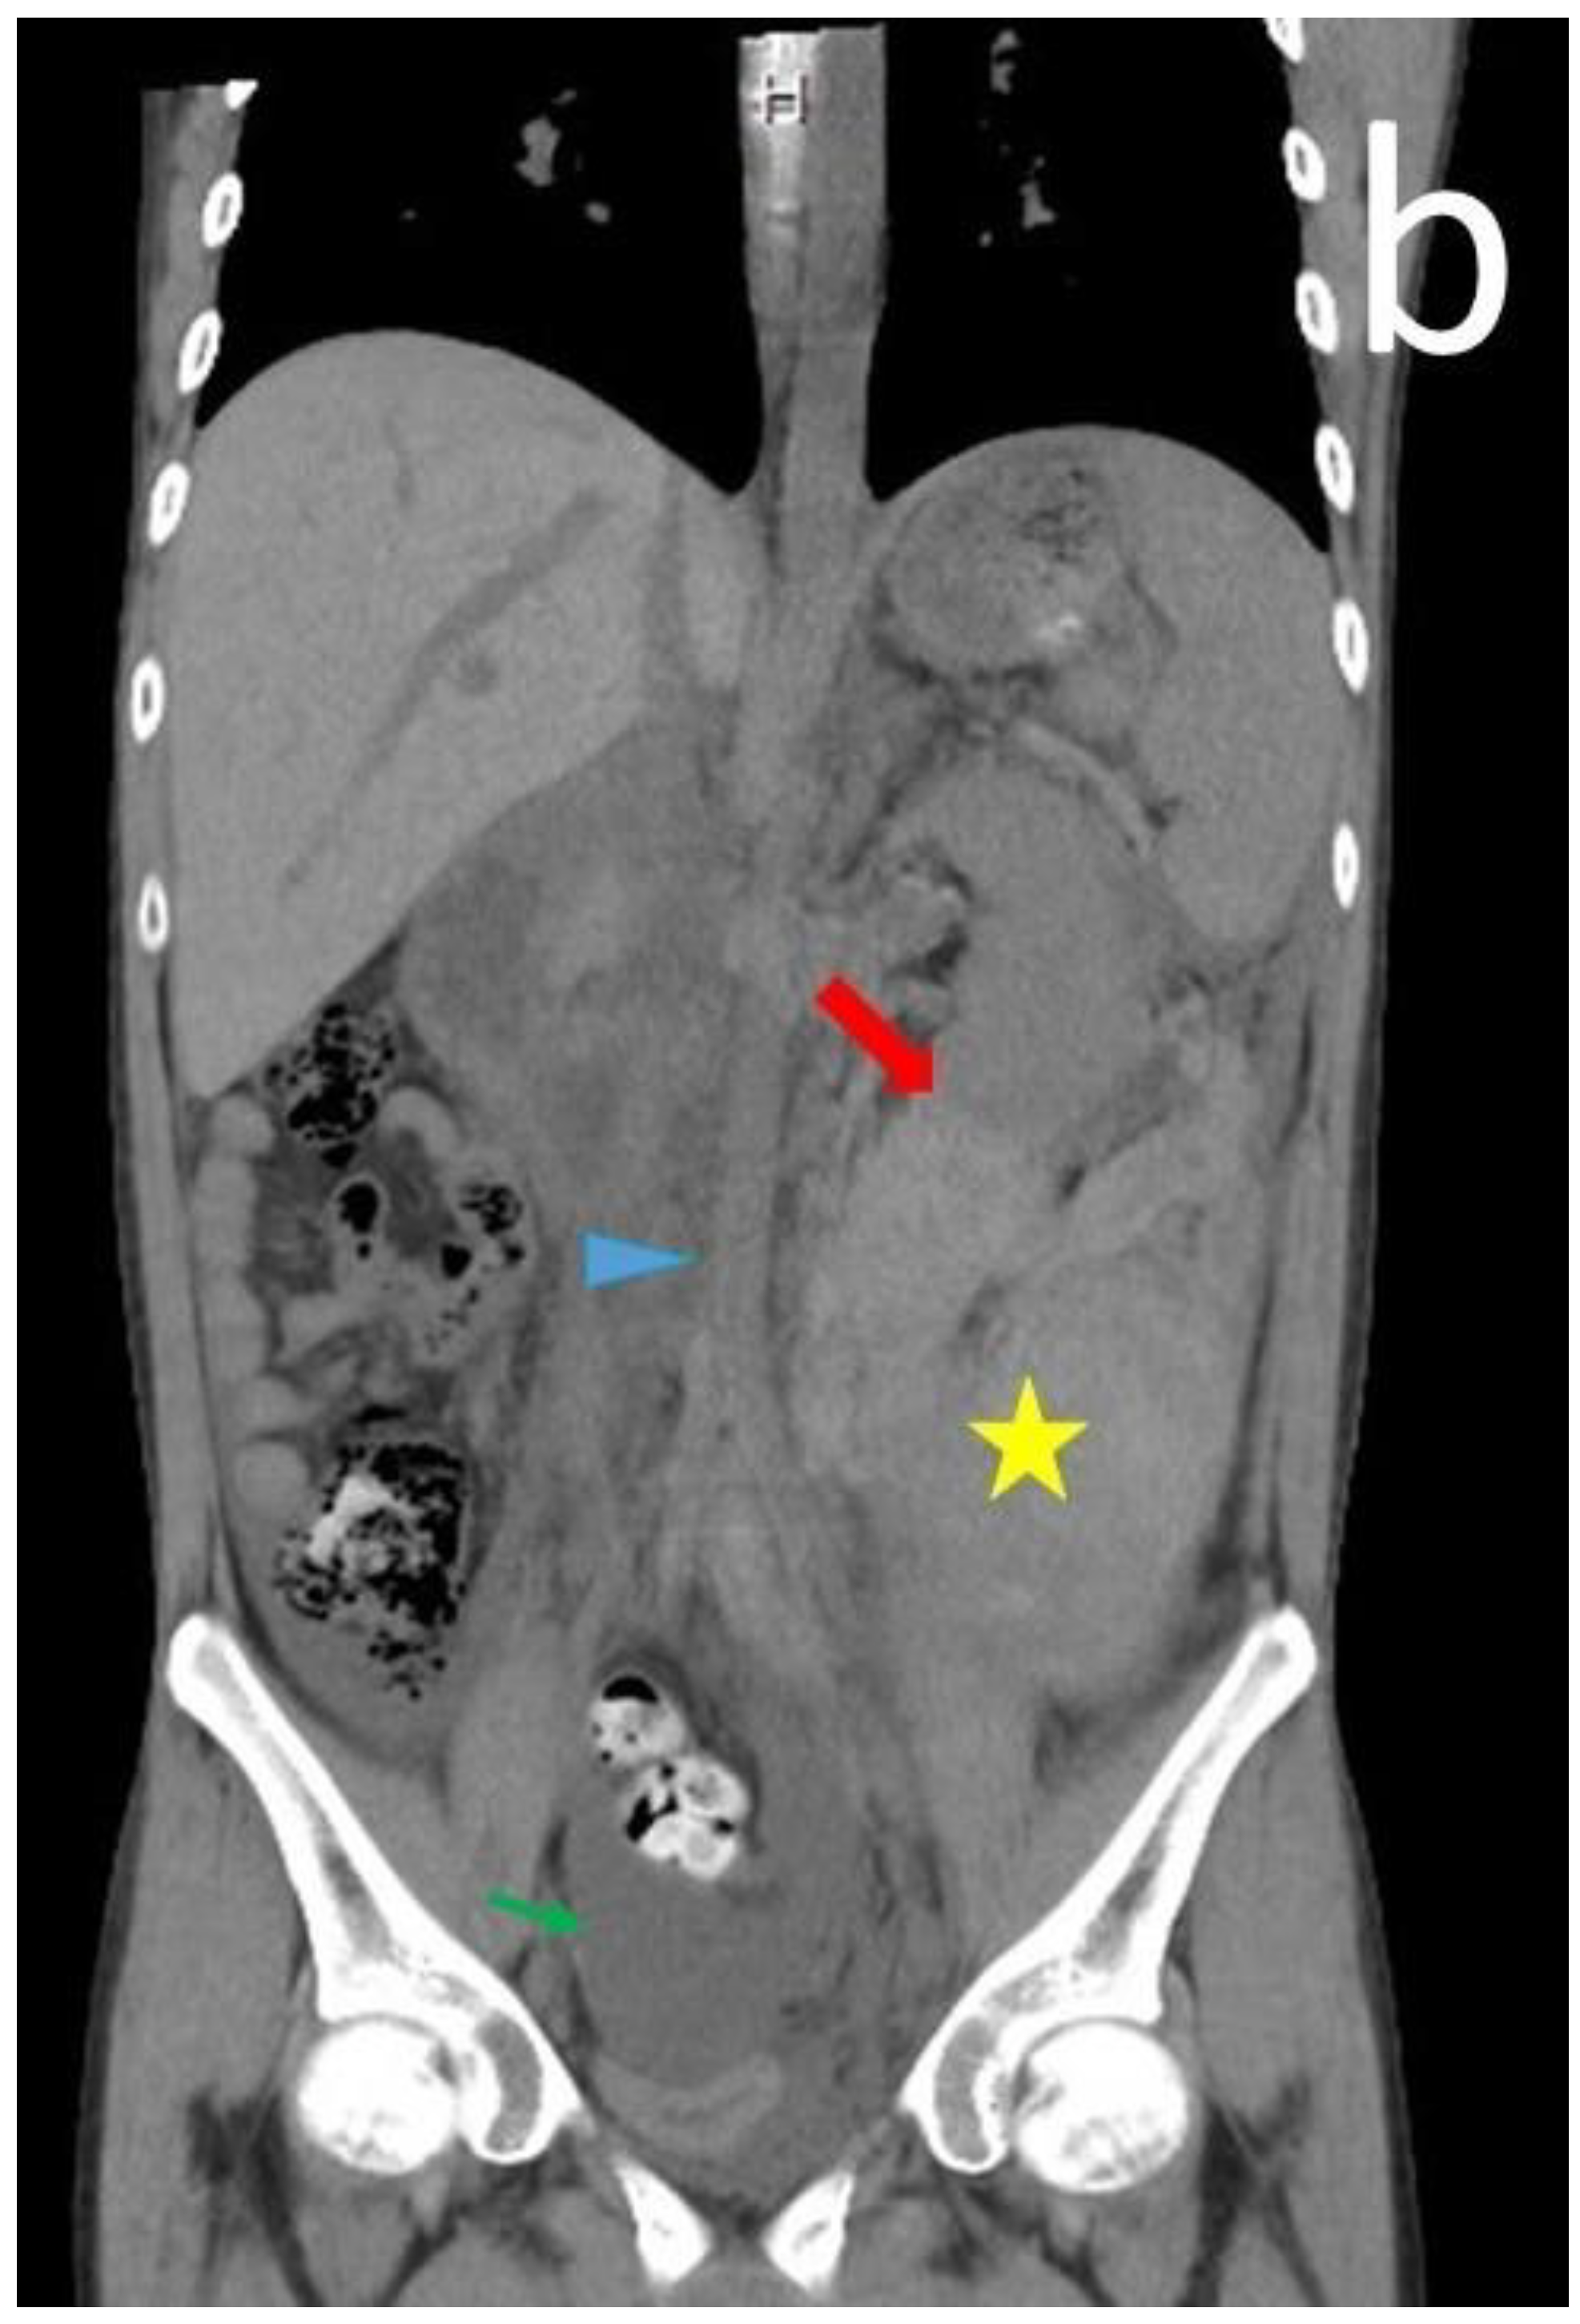

| 13 | Our case | 18 | Male | 12 | Flank pain Anemia(Hb: 6.7 g/dL) | Normal | Normal | CT | Angiodysplasia of the left renal artery & branch of IMA | N/A | Anti-dsDNA antibody Lupus anti-coagulant Anti-cardiolipin IgM | Embolization Steroid | N/A | Alive |